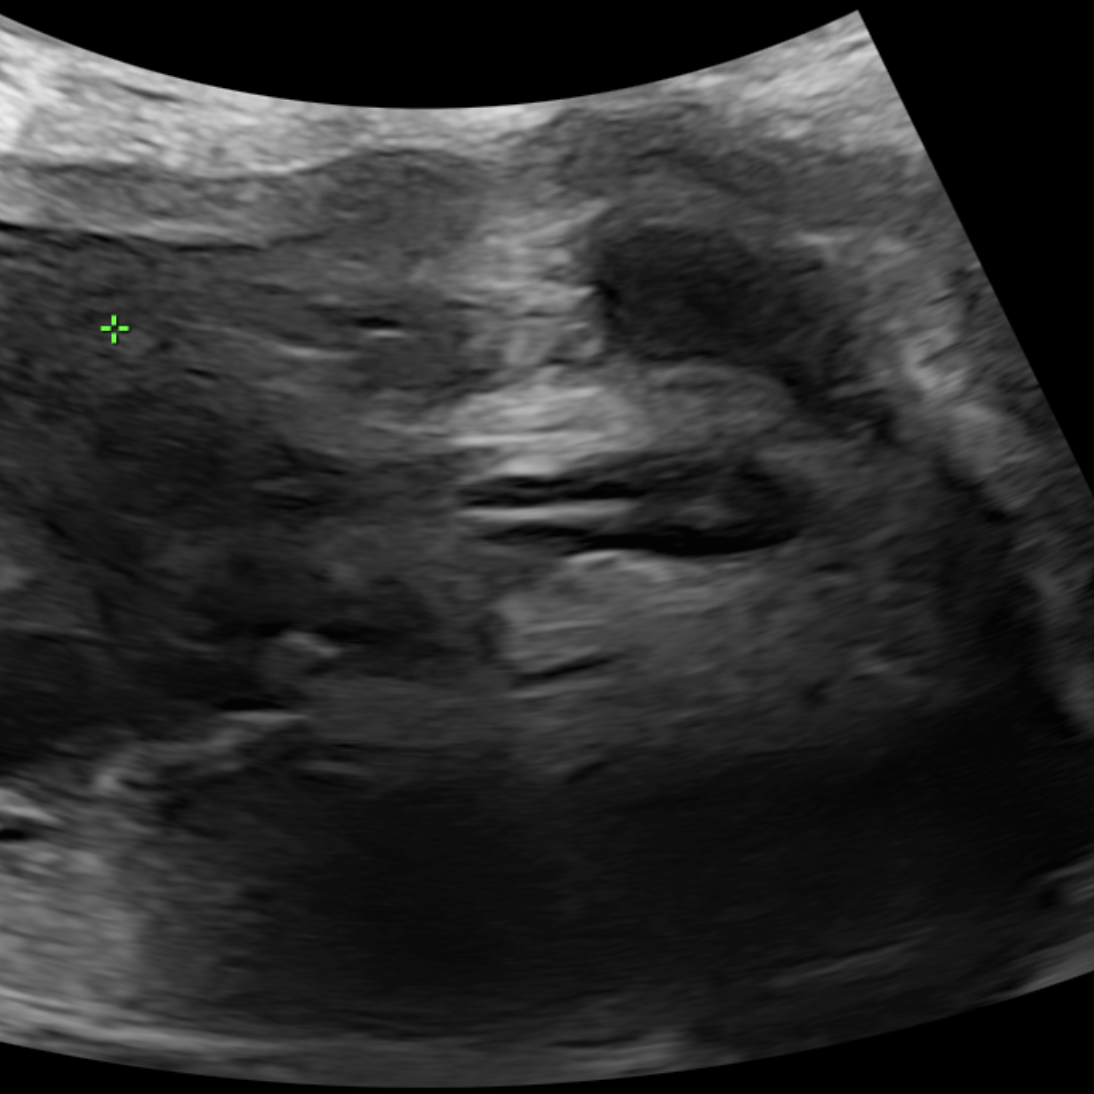

Tật nửa đốt sống - Hemivertebrea